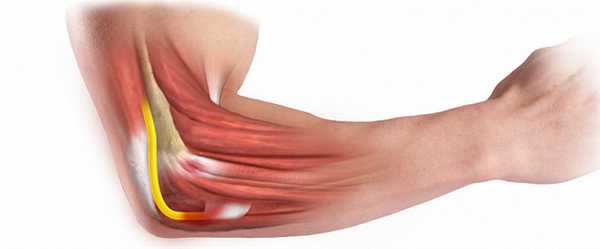

Суставная капсула локтевого сустава общая для трех суста-

вов, относительно свободная, слабо натянутая. К плечевой

кости капсула прикрепляется таким образом, что и венечная, и локтевая ямки плечевой кости находятся в полости сустава. Капсула более толстая по бокам, чем спереди и сзади. На уровне ямки локтевого отростка она особенно тонкая. Эта часть капсулы представляет наиболее слабое место капсулы сустава.

Суставная капсула локтевого сустава укреплена тремя связками. По бокам сустава в капсулу вплетаются прочные коллатеральные связки. Локтевая коллатеральная с в я з-к a, lig- collaterale ulndre, начинается от основания медиального надмыщелка плеча, веерообразно расширяется книзу и прикрепляется к внутреянему (медиальному) краю блоковидной вырезки локтевой кости. Лучевая коллатеральная связка, lig. collaterale radiale, толстая прочная, на плечевой кости начинается от латерального надмыщелка. Спускаясь к головке лучевой кости, делится на два пучка: передний и задний. Передний пучок'идет впереди, а задний — позади шейки лучевой кости, охватывая ее в в»де петли. Передний пучок прикрепляется у передненаружного края блоковидной вырезки локтевой кости, а задний пучок вплетается в кольцевую связку лучевой кости, lig. anulare radii. Последняя представлена пучком дугообразно изогнутых фиброзных волокон, которые охватывают шейку лучевой кости и прикрепляются у переднего и заднего краев лучевой вырезки лйктевой кости. Пучки волокон, соединяющие дистальный край лучевой вырезки локтевой кости с шейкой лучевой, носят название квадратной связки, lig. quad-ratum. Таким образом, кольцевая связка охватывает шейку лучевой кост^ и удерживает эту кость у латеральной поверхности локтевой кости.

Суставная капсула локтевого сустава общая для трех суставов, относительно свободная, слабо натянутая. К плечевой кости капсула прикрепляется таким образом, что и венечная, и локтевая ямки плечевой кости находятся в полости сустава. Капсула более толстая по бокам, чем спереди и сзади. На уровне ямки локтевого отростка она особенно тонкая. Эта часть капсулы представляет наиболее слабое место капсулы сустава.

Суставная капсула локтевого сустава укреплена тремя связками. По бокам сустава в капсулу вплетаются прочные коллатеральные связки. Локтевая коллатеральная с в я зк a, lig. collaterale ulnare, начинается от основания медиального надмыщелка плеча, веерообразно расширяется книзу и прикрепляется к внутреннему (медиальному) краю блоковидной вырезки локтевой кости. Лучевая коллатеральная связка, lig. collaterale radiale, толстая прочная, на плечевой кости начинается от латерального надмыщелка. Спускаясь к головке лучевой кости, делится на два пучка: передний и задний. Передний пучок идет впереди, а задний - позади шейки лучевой кости, охватывая ее в виде петли. Передний пучок прикрепляется у передненаружного края блоковидной вырезки локтевой кости, а задний пучок вплетается в кольцевую связку лучевой кости, lig. anulare radii. Последняя представлена пучком дугообразно изогнутых фиброзных волокон, которые охватывают шейку лучевой кости и прикрепляются у переднего и заднего краев лучевой вырезки локтевой кости. Пучки волокон, соединяющие дистальный край лучевой вырезки локтевой кости с шейкой лучевой, носят название квадратной связки, lig. quadratum. Таким образом, кольцевая связка охватывает шейку лучевой кости и удерживает эту кость у латеральной поверхности локтевой кости.

Связки локтя

Общая суставная сумка, окружающая локоть, не настолько прочна, чтобы удерживать все крупные кости верхней конечности в едином суставе, особенно с внутренней стороны. Высокие нагрузки на руки во время выполнения физической работы и спортивных тренировок неизменно приводили бы к повреждениям локтя, если бы не прочный связочный аппарат, надёжно удерживающий локоть и обеспечивающий его ограниченную подвижность. К нему относятся следующие волокна:

- Лучевая коллатеральная связка соединяет надмыщелок плечевой и головку лучевой костей, затем расщепляется на два пучка и, охватывая головку в своеобразное кольцо, закрепляется на лучевой вырезке локтевой кости. В процессе жизнедеятельности верхняя часть этого кольца постепенно сплетается с сухожилиями, отвечающими за разгибание, частично выполняя их функцию и предотвращая перерастяжение; а глубокие волокна формируют единую структуру с кольцевой связкой.

- Локтевая коллатеральная связка протянута от медиального надмыщелка плечевой до блоковидной вырезки локтевой кости. Совместно с лучевой коллатеральной эта связка ограничивает подвижность локтя, предотвращая боковые движения.

- Кольцевая связка представляет собой своеобразное «уплотнительное кольцо», которое охватывает суставную окружность головки лучевой кости, дополнительно фиксируя её у локтевой.

- Квадратная связка соединяет локтевую косточку с шейкой лучевой, надёжно фиксируя их друг у друга и препятствуя расхождению или перерастяжению.

Говоря о связочном аппарате локтевого сустава человека, невозможно не упомянуть о межкостной перепонке — особой структуре, которая анатомически хоть и не относится к связкам, но выполняет с ними единую функцию, фиксируя кости предплечья в отделах сустава. Она заполняет собой небольшую щель, образованную поверхностями лучевой и локтевой костей, и образует прочный лучелоктевой синдесмоз. Плотно переплетённые волокна этой перепонки имеют специальные отверстия, через которые проходят сосуды и нервы локтя, а края служат местом прикрепления некоторых мышечных волокон.